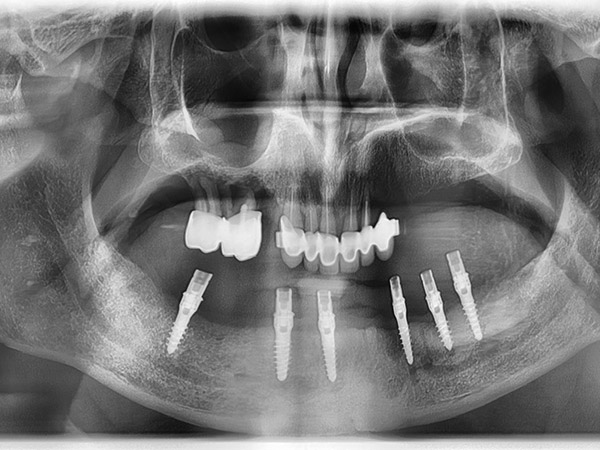

Sono state eseguite Tac con dima radiologica e progettazione per inserimento implantare tramite dima chirurgica di sei impianti AZ Implant tipo DX con overdenture a carico immediato.